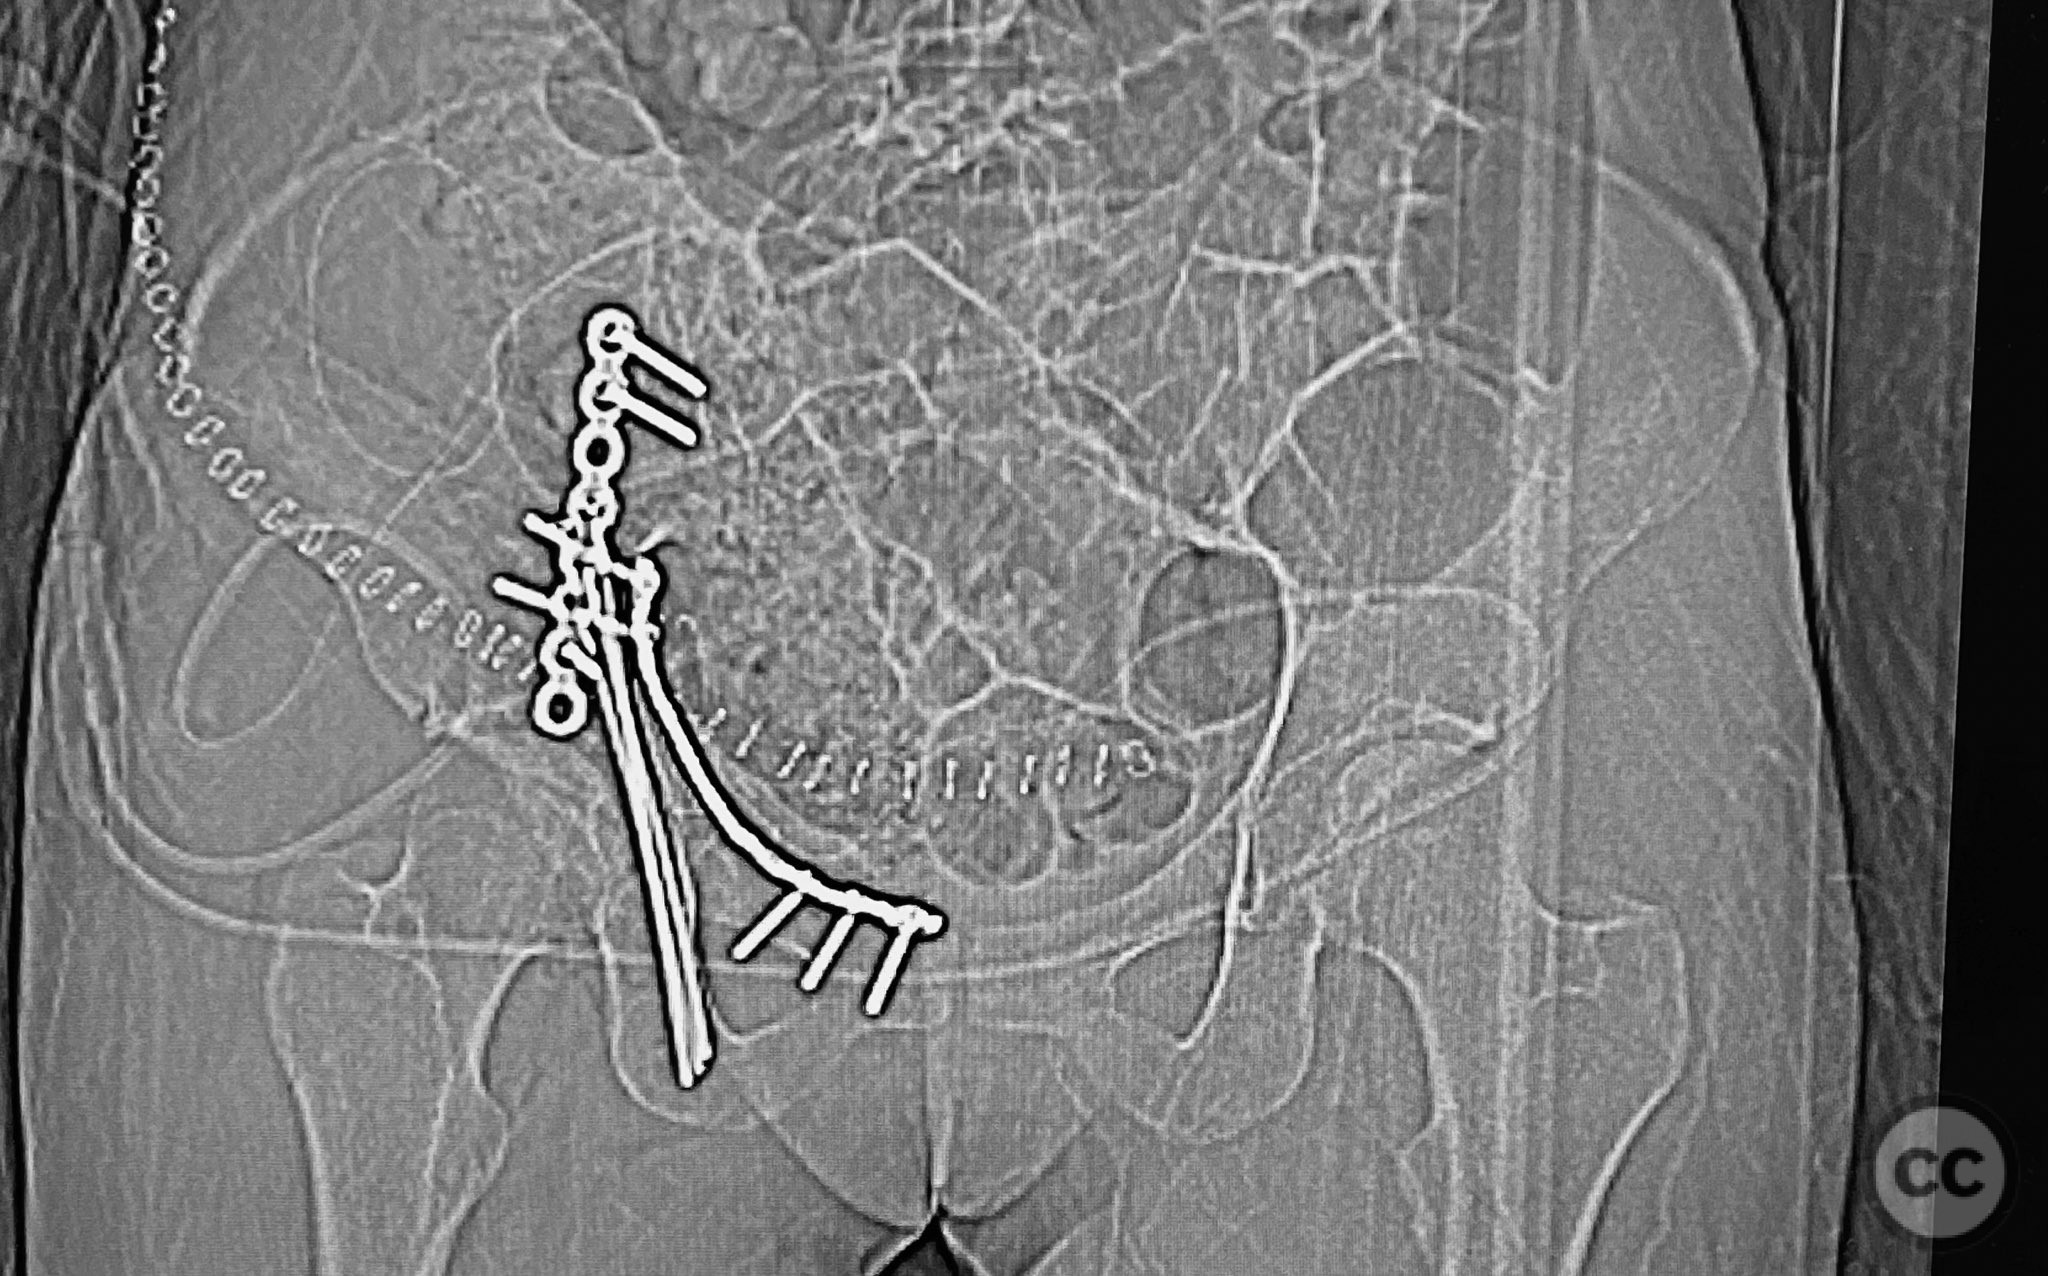

Clinical and radiological findings:  The patient sustained an acetabular fracture with a rare posterior medial dome impaction fragment, as demonstrated on AP pelvic radiographs obtained in skeletal traction. Surface renderings and axial CT images revealed multiple incomplete fracture lines, including a rhomboid-shaped cortical fragment adjacent and proximal to the anterior column/wall fragment. Coronal and sagittal reconstructions further delineated the impacted articular fragment and its relationship to the surrounding acetabular dome. The fracture pattern is classified as AO/OTA 62B3 (associated both-column fracture with dome impaction).

Anatomical surgical approach:  A classical ilioinguinal approach was performed, developing the lateral, middle, and medial windows. The intrapelvic interval was used to access the quadrilateral surface and posterior column. The rhomboid cortical fragment was excised to allow direct visualization and manipulation of the impacted posterior medial dome fragment. Reduction was achieved using a spiked pusher under fluoroscopic guidance. The defect was filled with morselized allograft, and the rhomboid fragment was anatomically reduced. The anterior column was stabilized with a contoured plate. Posterior column reduction was further improved using a reduction clamp applied with one tine lateral to the anterior inferior iliac spine (AIIS) and the other on the quadrilateral surface via the middle window, followed by lag screw fixation.

This case demonstrates that certain impacted dome fragments, which are otherwise inaccessible, can be directly addressed by temporarily removing overlying cortical fragments. The ilioinguinal approach, specifically through the middle window, provided unobstructed access for clamp placement and direct manipulation of both anterior and posterior column fragments. Sequential reduction and stabilization were facilitated by direct visualization and intraoperative fluoroscopy, allowing for anatomical restoration of the articular surface.

Orthopaedic implants used:   Contoured intrapelvic reconstruction plate, contoured anterior column plate, lag screws, morselized allograft